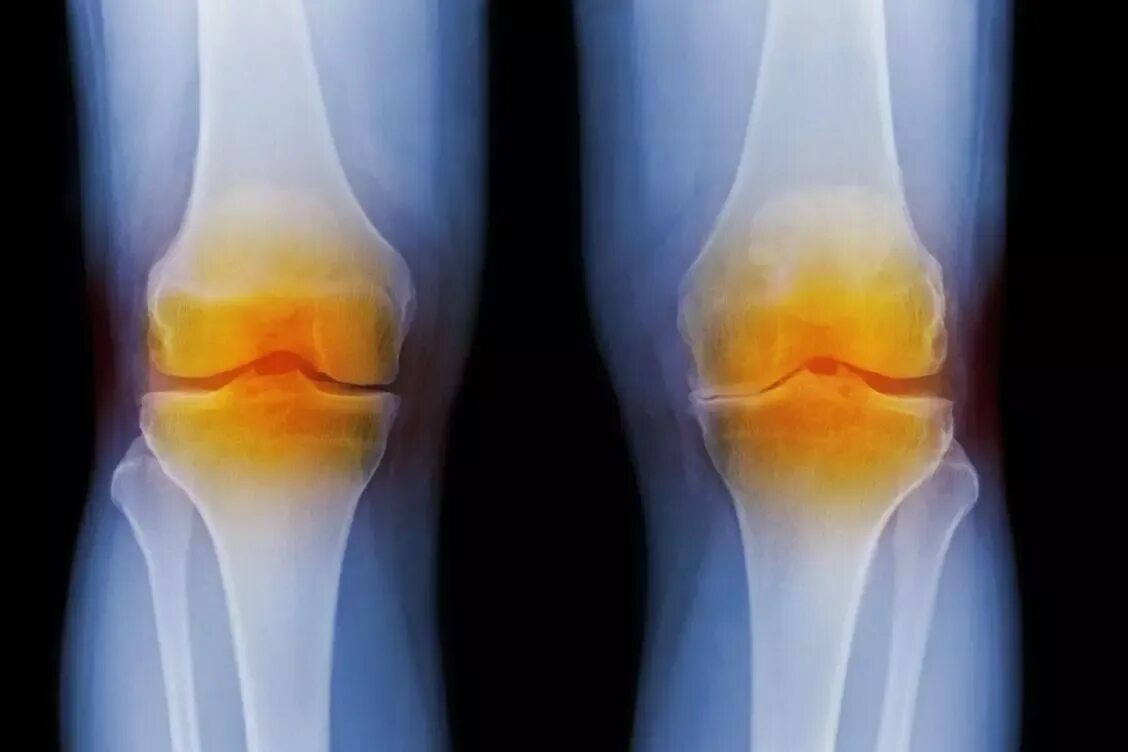

Какой врач лечит артрозы и артриты суставов